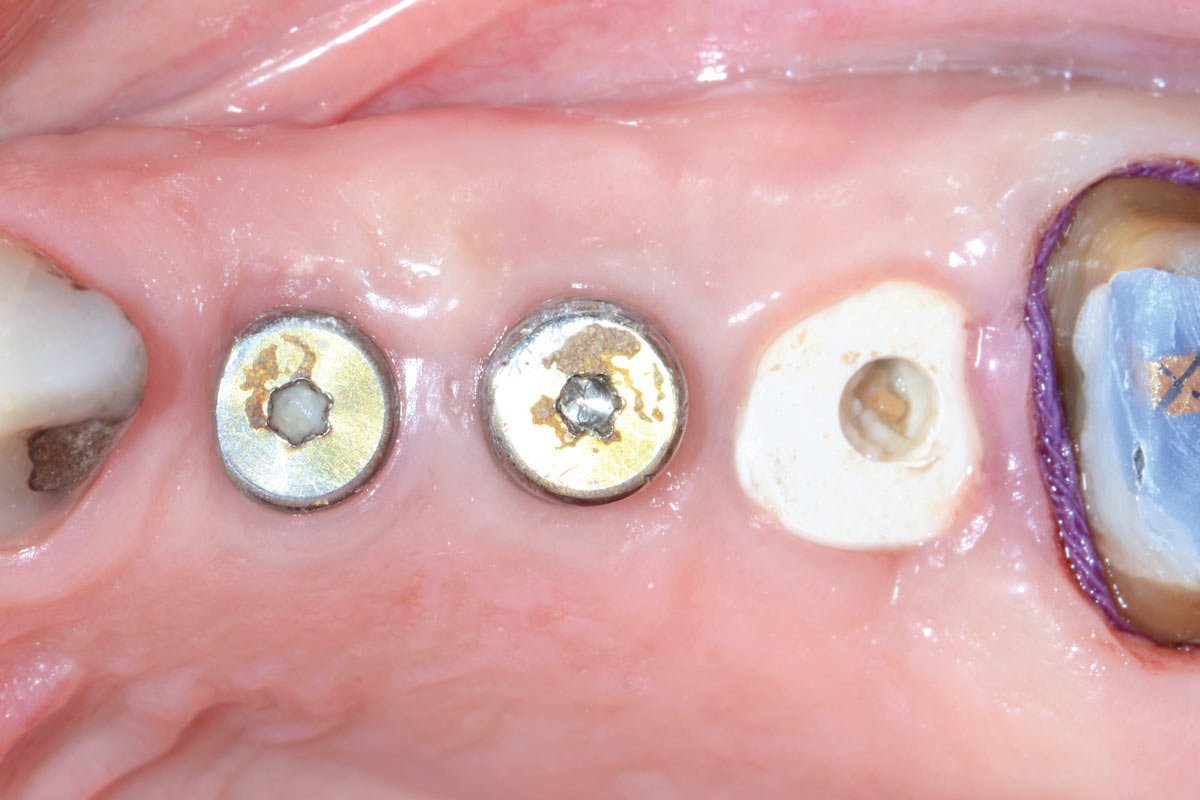

5/13 - Immediate placement of healing abutments

Multiple socket preservation in the maxilla with collacone® max – Dr. D. Jelušić